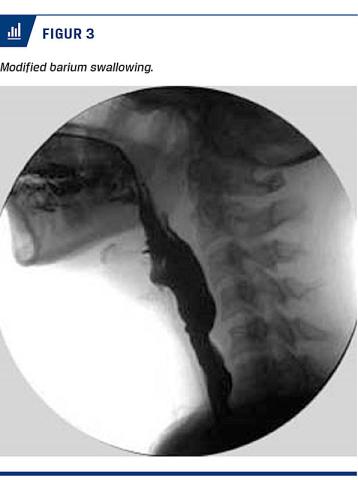

Ved MBS undersøges synkefunktionen ved røntgengennemlysning i forbindelse med indtag af forskellige konsistenser af føde og væske tilsat røntgenfast farvestof. Her visualiseres bevægelser og koordination

under synkning, og unormal orofaryngeal og øsofageal anatomi kan påvises (Figur 3). Graden og frekvensen af retention, penetration og aspiration kan bestem-

mes.